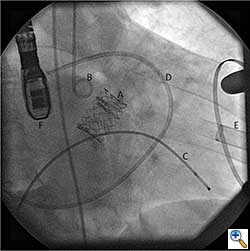

The Sapien valve is a balloon expandable platform and it comes in two sizes, 23 mm and 26 mm. The valve is prepared and mounted onto a sheath system for implantation on the back table. The femoral arterial access is serially dilated to accommodate a 22 French (for 23 mm Sapien valve) or a 24 French (for 26 mm Sapien valve) sheath. The balloon mounted valve is then advanced in a retrograde fashion into the aortic valve position using angiographic and echocardiographic guidance (Figure 2). It is important to visualize the position of the valve using at least 2 different angles. For the transfemoral approach, the recommended positioning of the prosthesis is 60%-40%, which is 60% of the prosthesis should be on the ventricular side of the aortic annulus with 40% of the prosthesis on the aortic side of annulus. This is due to the past experience observation that the prosthesis has a tendency to migrate in the aortic direction during deployment. This phenomenon is likely a result of the stored torque in the delivery system when introduced from the femoral artery. For ease of prosthesis arch transit, the delivery platform is equipped with the Retroflex system from Edwards. Of note, the correct orientation of the prosthesis should be confirmed both visually prior to placement into the introducer sheath and angiographically prior to deployment. Next, transvalvular flow is severely depressed by rapid ventricular pacing. The valve is then balloon expanded rapidly and implanted in position. If there is moderate to severe aortic insufficiency from a paravalvular leak after the deployment, a second ballooning with a larger volume is performed under conditions of rapid ventricular pacing.